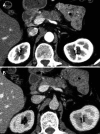

Significant advances in imaging technology have changed the management of pancreatic cancer. In computed tomography (CT), this has included development of multidetector row, rapid, thin-section imaging that has also facilitated the advent of advanced reconstructions, which in turn has offered new perspectives from which to evaluate this disease. In magnetic resonance imaging, advances including higher field strengths, thin-section volumetric acquisitions, diffusion weighted imaging, and liver specific contrast agents have also resulted in new tools for diagnosis and staging. Endoscopic ultrasound has resulted in the ability to provide high-resolution imaging rivaling intraoperative ultrasound, along with the ability to biopsy via real time imaging suspected pancreatic lesions. Positron emission tomography with CT, while still evolving in its role, provides whole body staging as well as the unique imaging characteristic of metabolic activity to aid disease management. This article will review these modalities in the diagnosis and staging of pancreatic cancer.